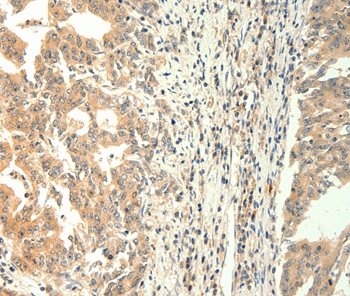

Immunohistochemical analysis of paraffin-embedded Human gastric cancer tissue using #37284 at dilution 1/60.